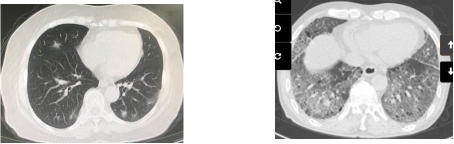

图1A 新冠患者A肺CT 图1B 新冠患者B肺CT

图1 新冠病毒感染患者肺CT

满足以下条件的患者可考虑进行APP治疗[2]:①新冠肺炎患者:使用HFNC或NIV时FiO2达0.3~0.6或鼻导管、面罩吸氧时氧流量达2~10 L/min以致外周血氧饱和度>94%;②影像学符合ARDS双侧重力依赖区浸润影的表现,如相比图1A患者,图1B患者将更可能通过APP治疗获益(图1)。